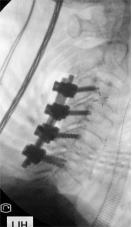

7. 复杂脊柱骨折内固定技术

随着区域内社会经济开发,复杂严重脊柱脊髓损伤病例增加,如何良好的手术治疗解除脊髓压迫、重建脊柱稳定性,使患者创伤最小、收益最大是促进患者康复至关重要的一环。性爱视频

已熟练开展各类脊柱损伤修复重建技术,每年完成复杂脊柱骨折手术处于区域领先水平。